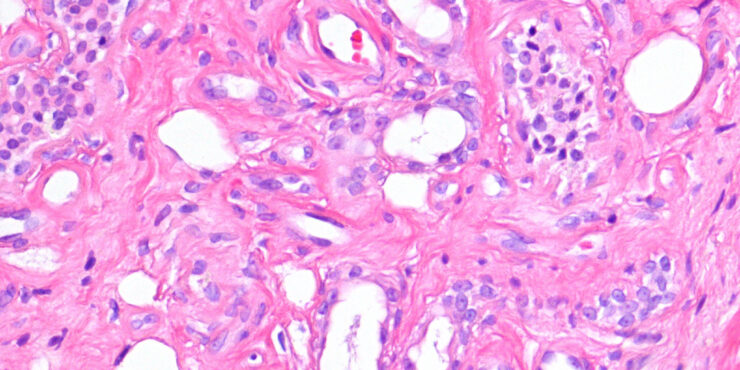

Early nodular Bcc =ورم قاعدي الخلايا عقيدي في مرحلة مبكرة